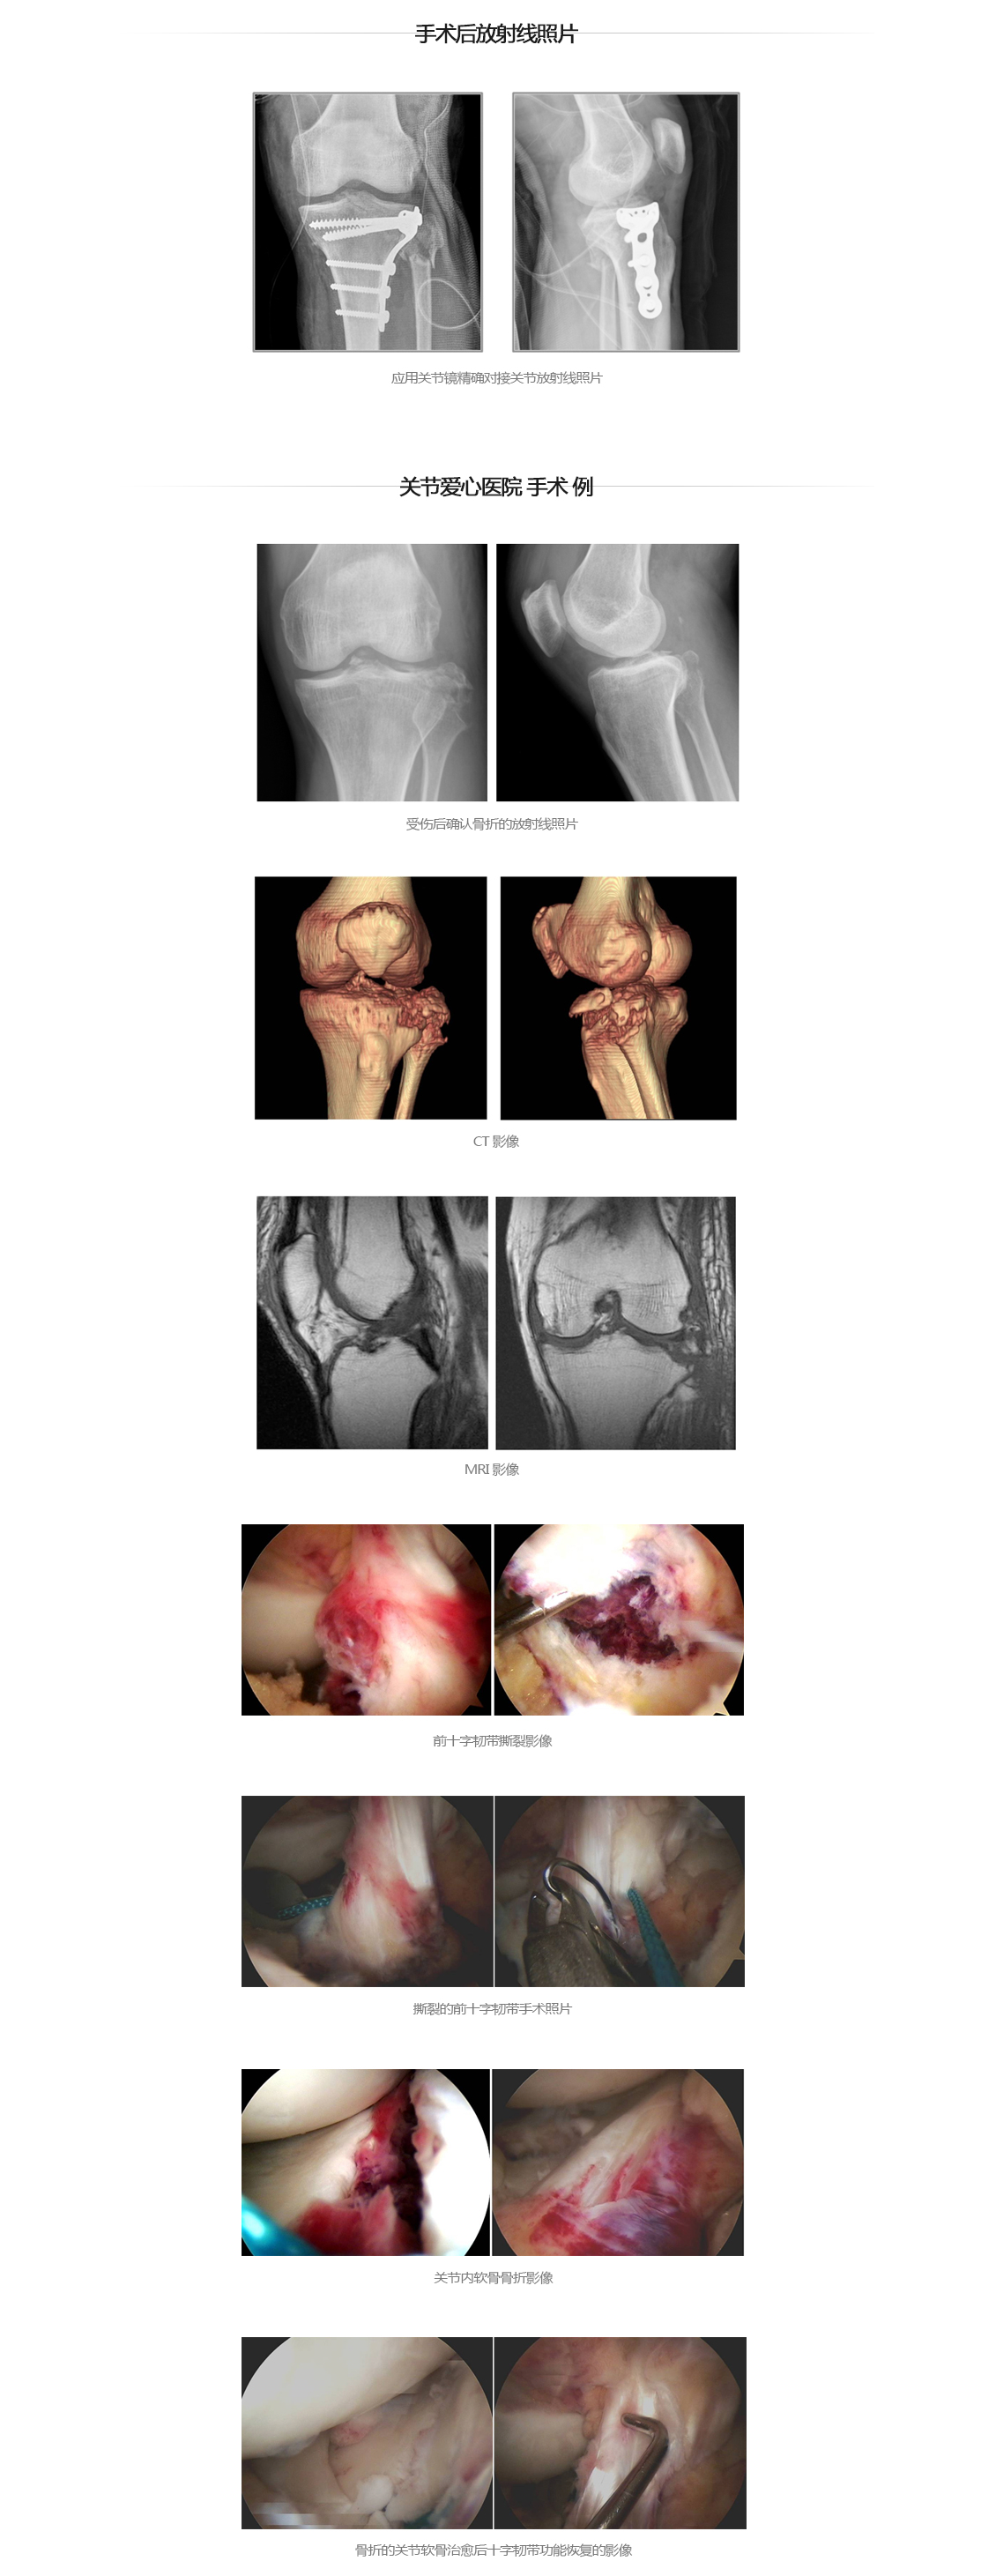

膝盖骨折手术